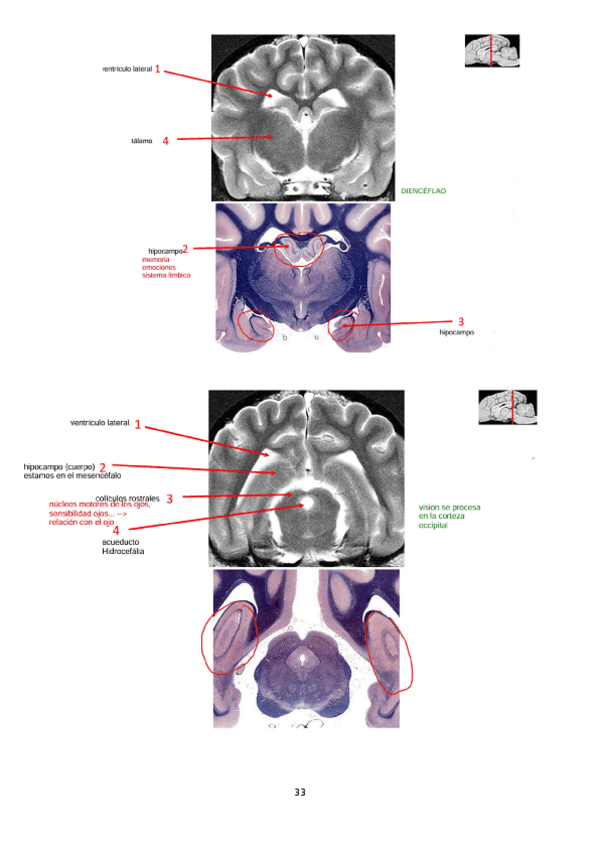

Seminario-neuroimagen.pdf

Respuestas del seminario de neuroimagen